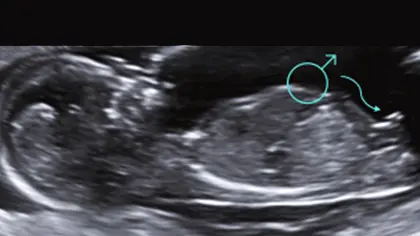

Revelación del Sexo Fetal

• ❤ Sabemos que conocer el sexo de tu bebé siempre será algo muy importante para ti, ¿Sabías que ya desde el primer trimestre podremos saber el sexo de tu bebé con una precisión de casi el 90%? A partir de la semana 16 ya se confirma el sexo en un 100%.

• ❤ La evaluación del sexo nos permitirá conocer algunas alteraciones de los genitales.

• ❤ Es importante también para descartar alteraciones genitales o enfermedades ligadas al sexo.